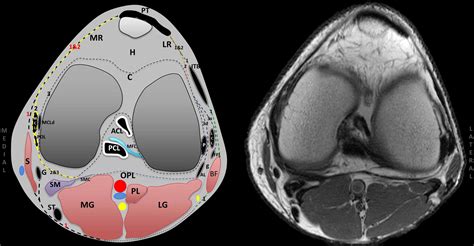

The posterolateral aspect of the knee is a sophisticated region composed of static and dynamic stabilizers. Understanding how these structures function together is essential to comprehending the mechanics of a Posterolateral Corner Injury. The main static stabilizers include:

• Lateral Collateral Ligament (LCL): The primary restraint against varus stress.

• Popliteus Tendon: Acts as a key stabilizer against external tibial rotation.

• Popliteofibular Ligament: Works in concert with the popliteus tendon for rotational stability.

• Arcuate Ligament Complex: Provides structural support to the posterior capsule.

Dynamic stabilizers, including the lateral head of the gastrocnemius muscle, the biceps femoris tendon, and the iliotibial band, also contribute to the overall tension of the knee joint. When these components are damaged, the joint loses its ability to track correctly, leading to functional instability and long-term risk of degenerative joint disease.